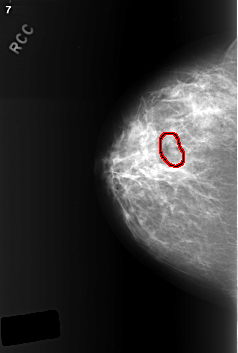

C_0402_1.RIGHT_CC

FILE: C_0402_1.RIGHT_CC.OVERLAY

TOTAL_ABNORMALITIES 1

ABNORMALITY 1

LESION_TYPE MASS SHAPE LOBULATED MARGINS CIRCUMSCRIBED

ASSESSMENT 3

SUBTLETY 4

PATHOLOGY BENIGN

TOTAL_OUTLINES 1

BOUNDARY